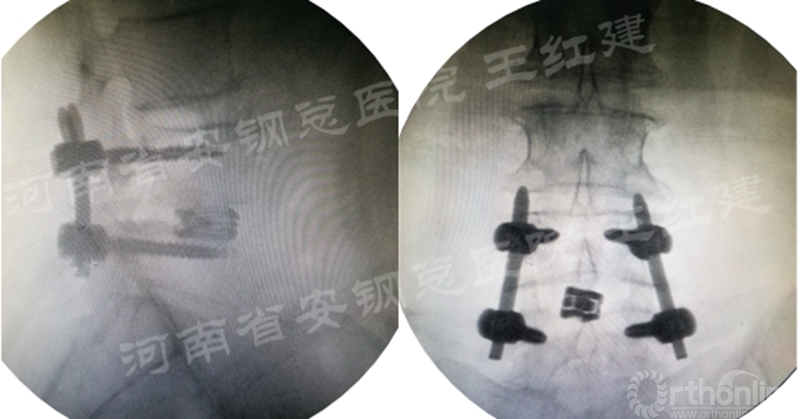

四、经皮螺钉技术固定

在固定的步骤可以先期进行经皮螺钉置入,再进行融合器的置入,进而实现充分固定。

椎弓根植入加压固定

单边椎弓根植入加压固定

双侧椎弓根植入加压固定

手术步骤:先期经皮螺钉置入、再进行融合器的置入

内镜辅助下的椎间融合技术具有临床实用性,真正实现微创下神经根的减压、椎间融合器的置入、撑开固定及滑脱复位,术后可获得与传统开放手术相同的影像学效果。

内镜技术可完成椎管的扩大、神经根的松解、直视下处理软骨终板;通道技术可以更加快捷的处理软骨终板,完成椎间植骨并融合器置入;经皮螺钉技术更有利于脊柱稳定,椎间融合以获得长期疗效。